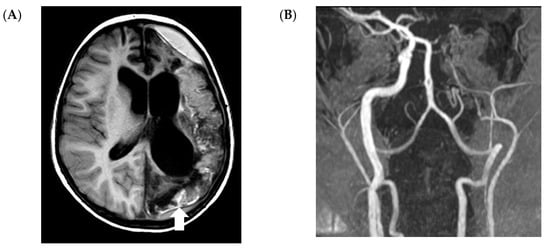

5.2. CNS Manifestations